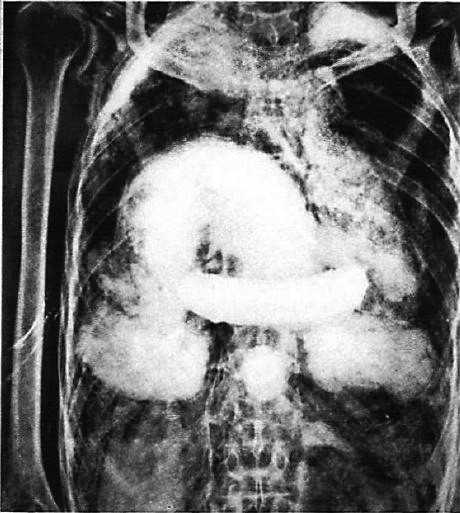

図9.ミイラのX線写真 [30]

レントゲンの論文が発表されてわずか3ヵ月後の1896年3月,ドイツの物理学者Walter Königは初のX線アトラスとも言える写真集[22]を出版したが,この中にヒトのミイラの膝,鳥のミイラの写真が含まれており,おそらく初のミイラのX線写真と思われる*.その後20年間,主にドイツ語圏でエジプトやペルーのミイラのX線撮影が散発的に報告されている[23](図30).当時,エジプトのミイラとされていたものの中には贋作も少なくなく,X線はそれらの鑑定にも有用であった.

しかし初の本格的なミイラのX線研究は,1967年の放射線科医Peter Grayによる論文で,イギリスおよびヨーロッパ各国の博物館所蔵のミイラ133体のX線検査を行ない,年代によって遺体処理方法が異なることを明らかにした.また中には贋作が含まれていることもわかった[→原著論文].1973年,イギリスの考古学者Harrisは,カイロ博物館所蔵のファラオのミイラの系統的調査結果を著した[25].このような方法は放射線考古学(Paleoradiology)と呼ばれるが,この言葉を初めて使用したのは,アメリカの放射線科医Derek Notmanで,1845~8年の北極探検中に遭難,全員が死亡したフランクリン遠征隊員2人の遺体のX線所見を報告した1987年の論文中に登場している[26].

図10.第21王朝期のミイラ.摘出内臓のパッケージが体腔内に認められる.

図11.後期の小児のミイラ.陶片,医師,砂などで充填されている.後期になると遺体の処理が次第に粗雑になった.

【要旨】ミイラ研究におけるX線利用は充分に研究されていない.そこで,ミイラを所蔵するイギリスおよびヨーロッパ各国の博物館に依頼して,133例(うち成人88例)のミイラのX線撮影を行った.検討したX線所見は,考古学的な側面については人骨の有無,年齢・性別,ミイラ作製法の確認,副葬品の確認,また古病理学的な面については,骨病変,軟部病変の評価である.

19世紀初頭に購入されたミイラは,棺の中身が空であったり,動物のミイラであったり,石と木が入れられた偽造品もあった.棺に描かれた性別,年代と内容が異なるものもあった.初期(2500 B.C.前後)は,臓器を摘出してカノポス壷に収めていた.ミイラ製作技術が大きく進歩した第18~20王朝(1567~1086 B.C.),技術が頂点に達した第21王朝(1085~935 B.C.)では,摘出した臓器を布に包んで,再び体腔に戻した(図10).第26王朝(664~525 B.C.)では内臓を体内に戻さず,包みを両脚の間においたり,再びカノポス壷を使用するようになった.プトレマイオス朝期(332~30 B.C.)になると頭蓋や体腔に樹脂を流し込むようになった.ミイラ製作は640 A.D.頃まで続いたが,製作法は次第に粗雑になり,体腔に石や砂が充填された例もあった(図11).病的所見としては,脊椎の骨関節炎(成人88例中17例),骨成長停止線(約30%),骨折,顎骨嚢胞,骨梗塞,内軟骨腫,骨形成不全症,動脈硬化性変化,胆石などが認められた.悪性腫瘍,結核,梅毒,癩病などの所見はなかった.

【解説】ミイラのX線撮影は,誰しも考えるところで,X線発見直後から散発的に行われていた.しかし,多数例を撮影して,ある程度まとまった所見を記載したのは,この論文が初めてである.

冒頭に当時のミイラ作製法が簡潔に述べられている.エジプトではもともと,遺体を砂に埋める風習があり,高温,乾燥した環境のため遺体はきれいに保存された.しかし死後の世界への信仰から大きな墓に入れるようになると,遺体が腐敗することからミイラ製作の技術が発展したという.内臓は側腹部の切開創から,脳は鼻孔から摘出したとの記載があり,いずれも狭い術野からどのように摘出したのか興味あるところであるが,この内臓の処理の仕方が年代により異なり,ミイラの年代推定の手がかりとなるという.時代が下るに従って,次第にミイラの作りが雑になってゆくという点も興味深い.

病的所見についてはあまり詳しく触れられていないが,変形性脊椎症,動脈硬化症が比較的多い.2018年に発表された過去の論文に記載された189例のエジプトミイラのメタ解析でもやはり同様の傾向が報告されている [31].